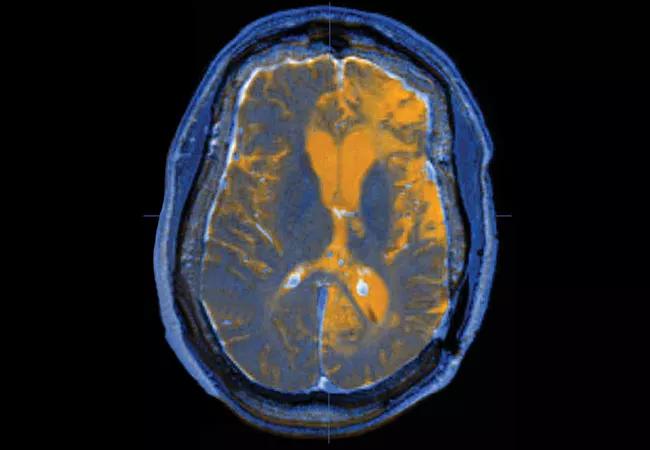

Image at top: Axial image of a patient with traumatic brain injury created by fusing T1 and T2 MRI data sets.